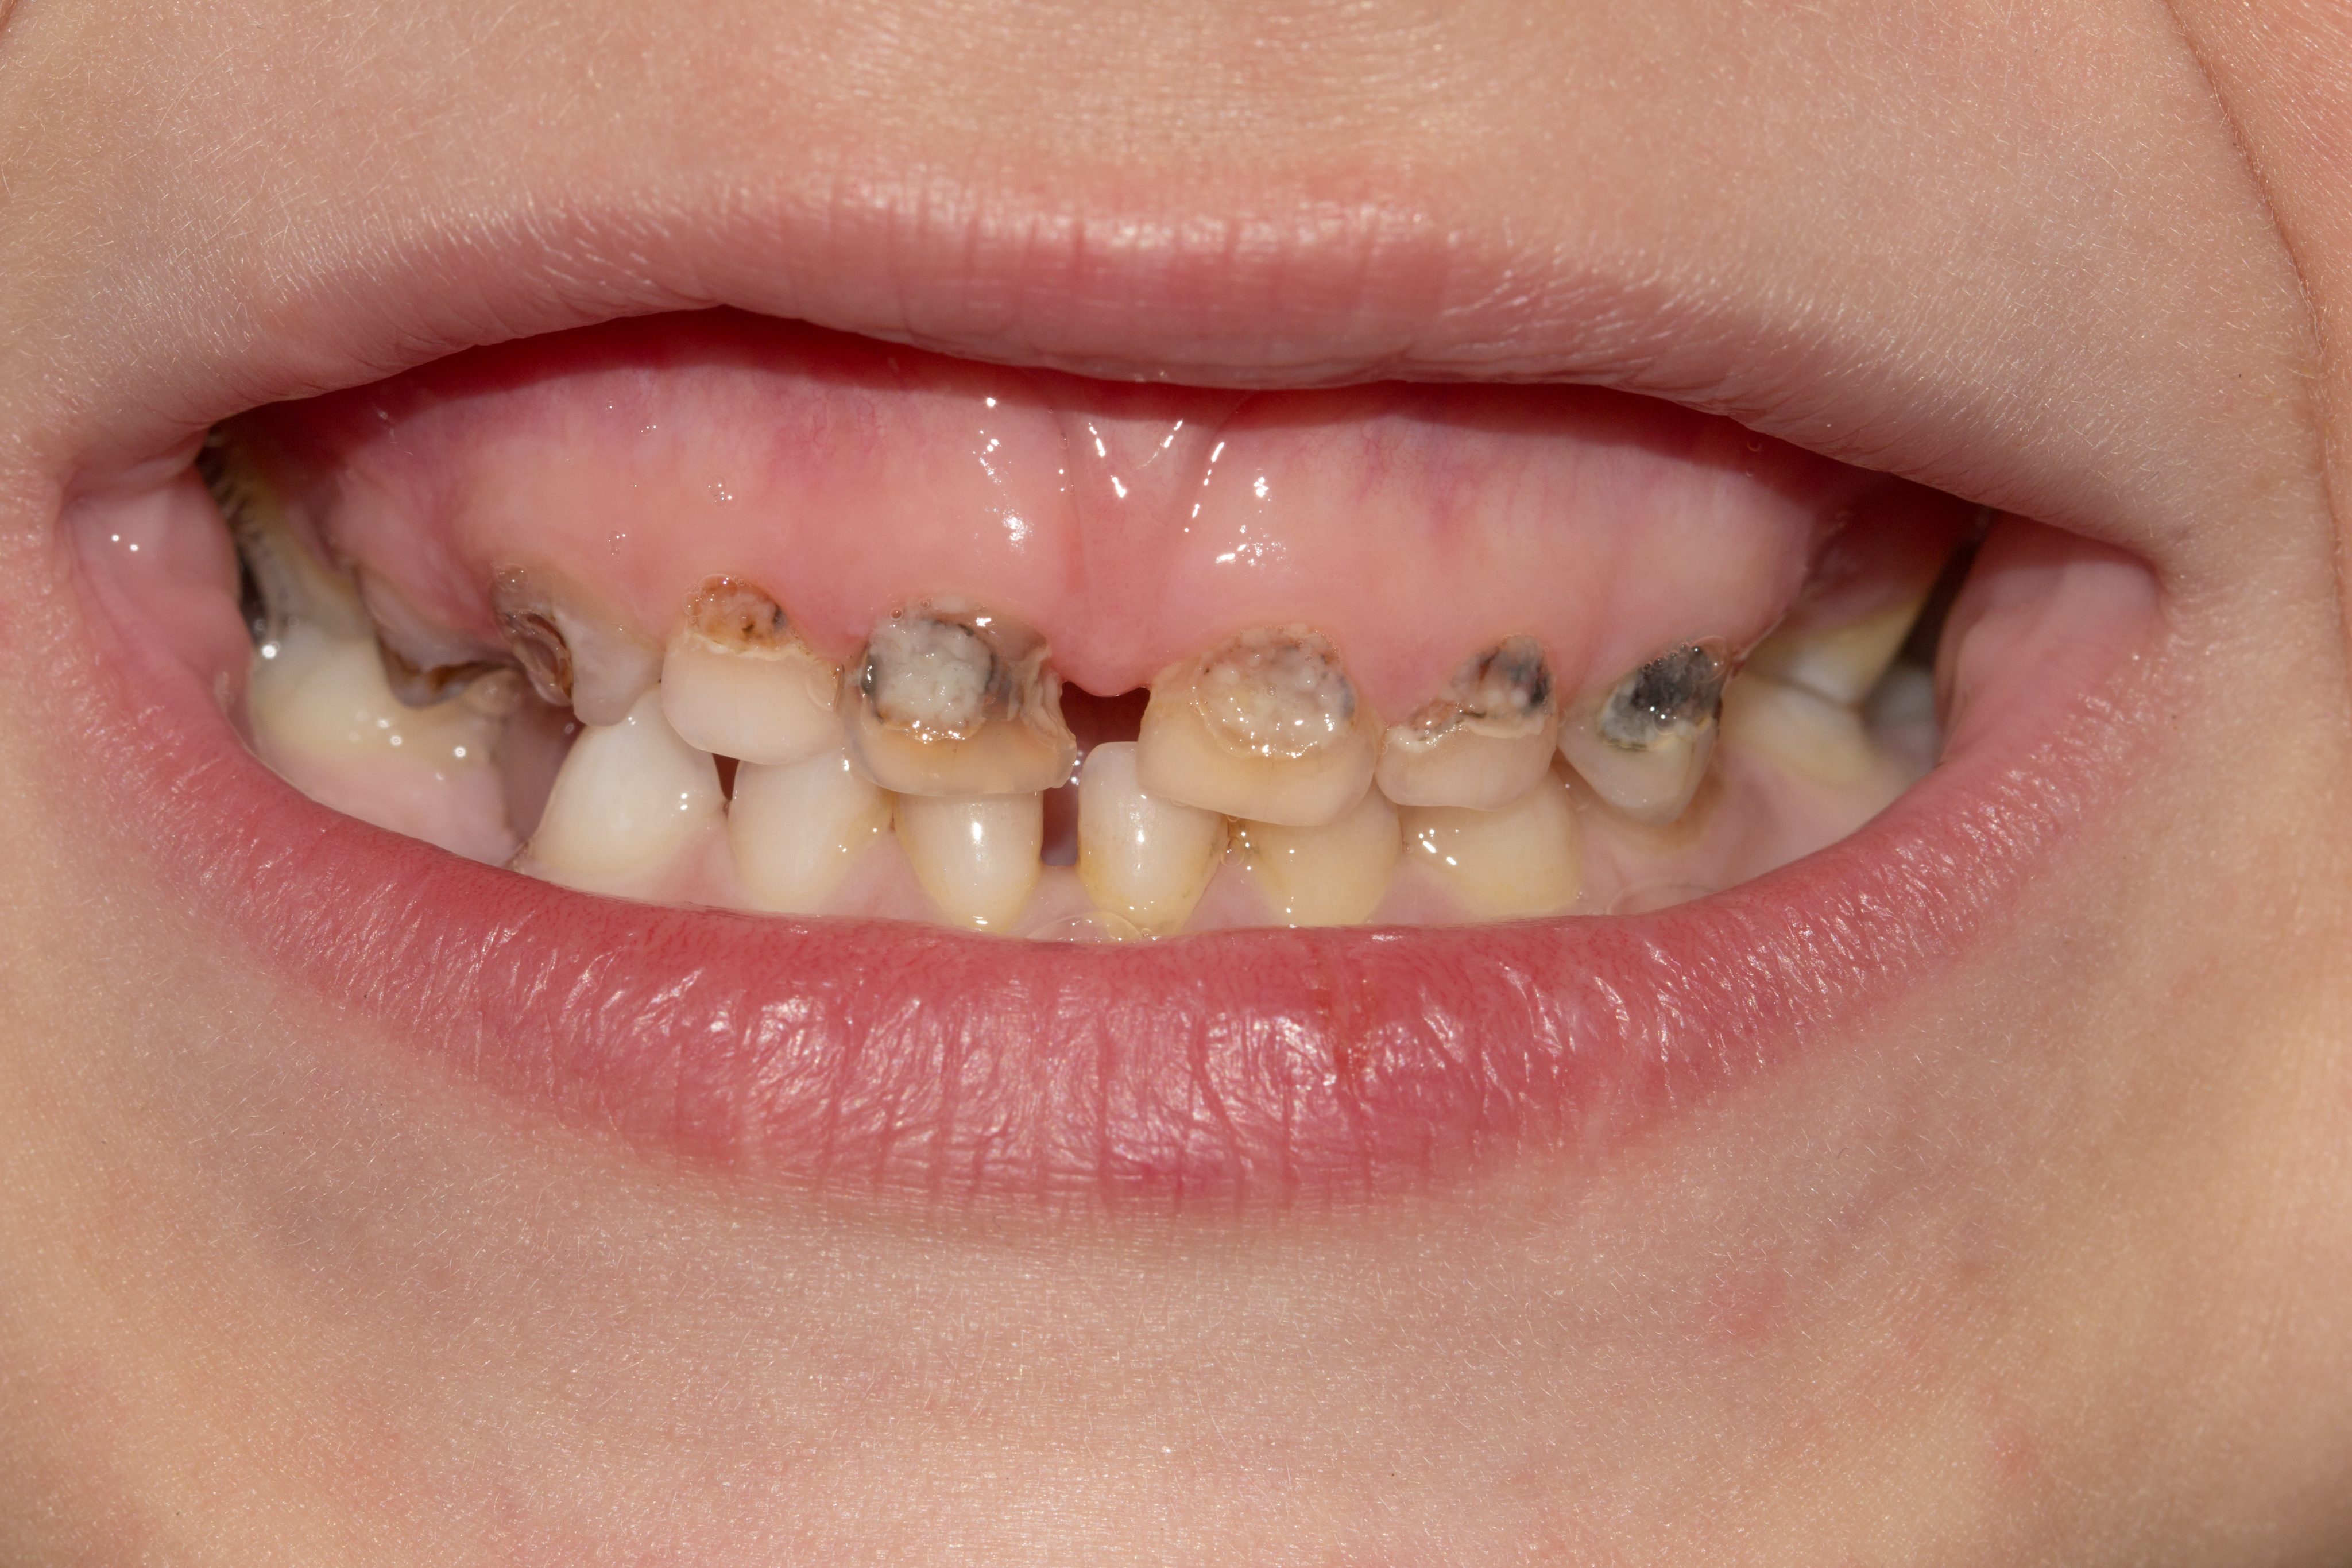

- Non-erupted tooth #8 and missing tooth #T

Cavitated lesions on teeth:#3-O #A-OBL,#14-O #19-O,#L-O, #S-O,and #30-OB

Figures 4,5 & 6: Posterior right, anteriors, and posterior left